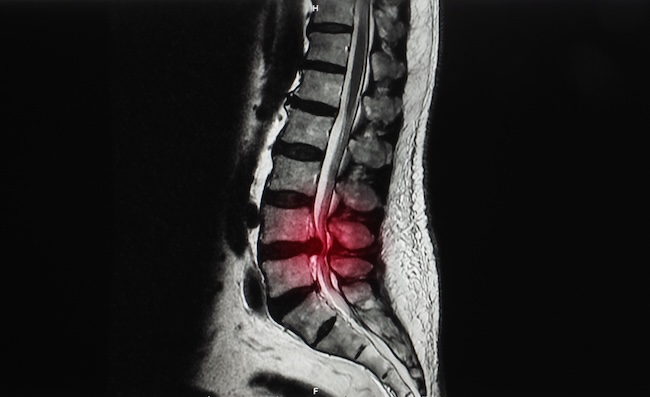

Hernia nukleus pulposus pada area lumbar dapat menyebabkan keluhan nyeri punggung bawah, skiatika, dan klaudikasio yang dapat mengganggu kualitas hidup penderita. Pada kondisi tertentu, atau ketika terapi konservatif gagal mengatasi masalah ini, maka tindakan operasi menjadi pilihan. Pada mulanya tindakan operasi terbuka atau operasi mikro merupakan pendekatan yang paling banyak digunakan, tetapi seiring dengan kemajuan teknologi tindakan operasi dengan metode endoskopi menjadi teknik yang lebih disukai.[1-4]

Endoscopic lumbar discectomy dan disektomi terbuka adalah dua prosedur yang digunakan untuk mengatasi hernia nukleus pulposus pada tulang belakang bagian lumbar. Perbedaan utama antara keduanya terletak pada metode akses dan invasivitas prosedur.

Di sisi lain, endoscopic discectomy menggunakan pendekatan invasif minimal, di mana alat endoskopi dimasukkan melalui sayatan kecil pada kulit dan dipandu menuju area yang terkena tanpa harus membuka jaringan secara luas. Jenis endoscopic discectomy yang umum dilakukan termasuk percutaneous endoscopic discectomy (PED) dan full lumbar endoscopic discectomy (FLED).[1,3-7]